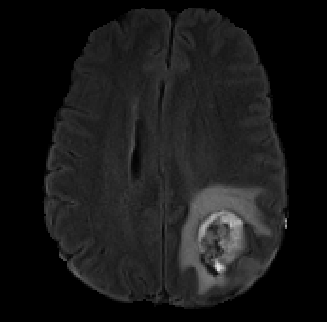

Data augmentation has been widely used for training deep learning systems for medical image segmentation and plays an important role in obtaining robust and transformation-invariant predictions. However, it has seldom been used at test time for segmentation and not been formulated in a consistent mathematical framework. In this paper, we first propose a theoretical formulation of test-time augmentation for deep learning in image recognition, where the prediction is obtained through estimating its expectation by Monte Carlo simulation with prior distributions of parameters in an image acquisition model that involves image transformations and noise. We then propose a novel uncertainty estimation method based on the formulated test-time augmentation. Experiments with segmentation of fetal brains and brain tumors from 2D and 3D Magnetic Resonance Images (MRI) showed that 1) our test-time augmentation outperforms a single-prediction baseline and dropout-based multiple predictions, and 2) it provides a better uncertainty estimation than calculating the model-based uncertainty alone and helps to reduce overconfident incorrect predictions.